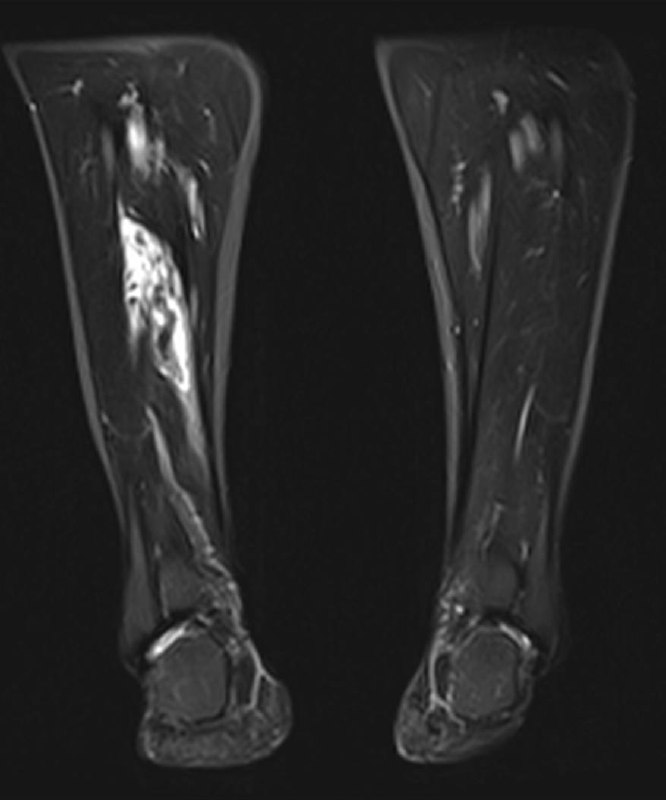

23 года, мужчина, 20 октября на матче что-то "щёлкнуло" в колене